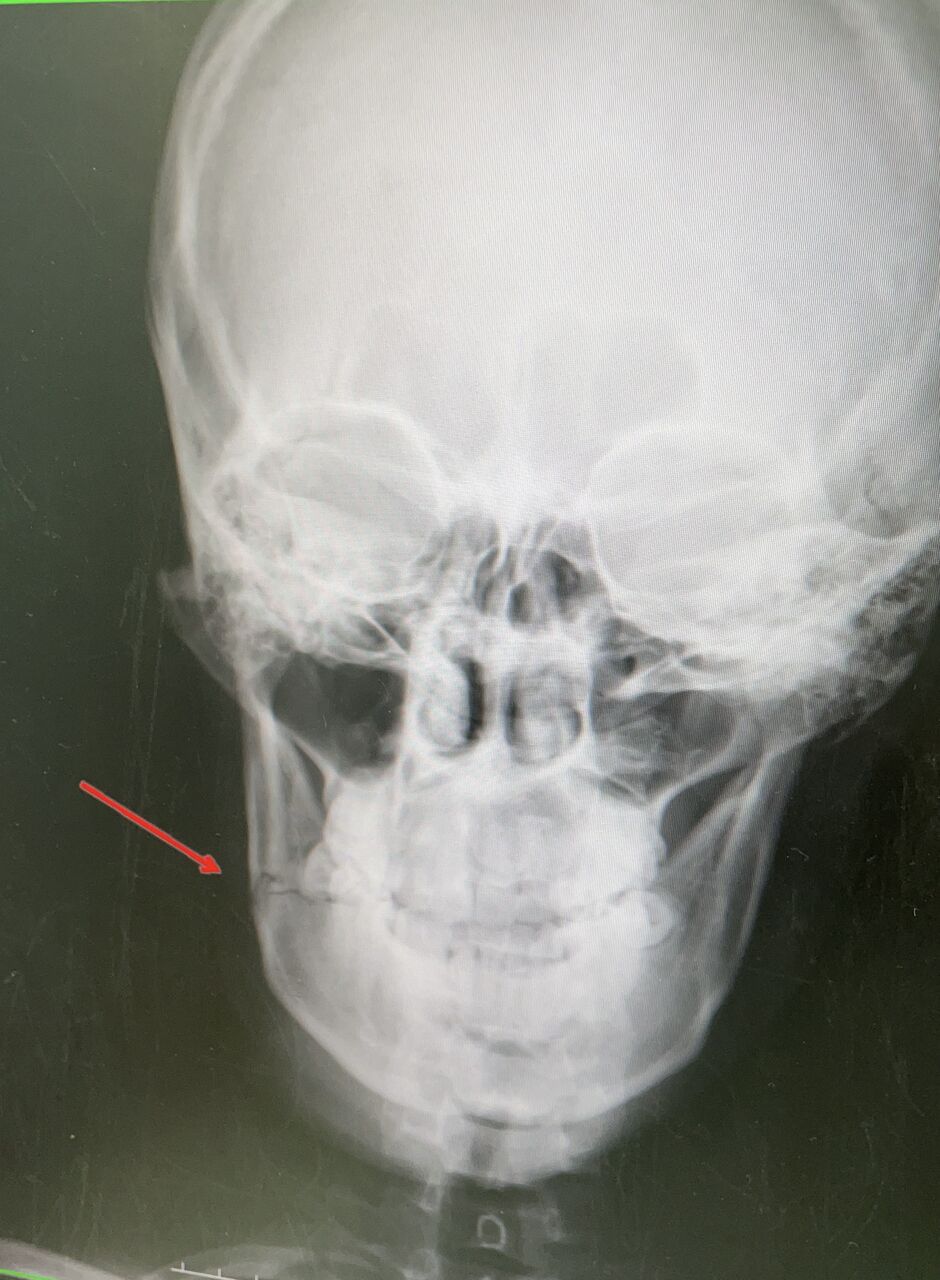

キックボクシング

プロトーナメント リングでの戦いのあと

蹴りが、顔面にヒットして

顔面骨折の相談です

口腔外科の先生と、連携しながら

治療いたします